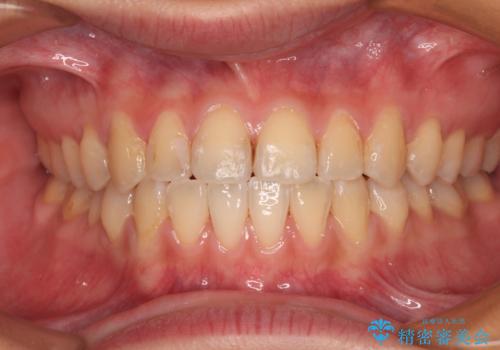

前歯のクロスバイトを治したい ワイヤー装置による矯正治療

クロスバイト改善まではスムーズに進みましたが、その後は強い舌の突出癖によりオープンバイトの期間が長く続きました。

舌のトレーニングをしっかりと実施してもらい、何とか仕上げることができました。